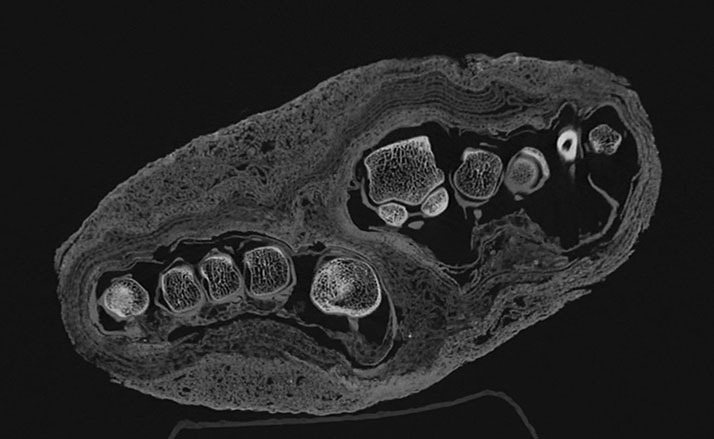

Medical Imaging Center, MNMKK Semmelweis Museum of Medical History

Medical Imaging Center, MNMKK Semmelweis Museum of Medical History -